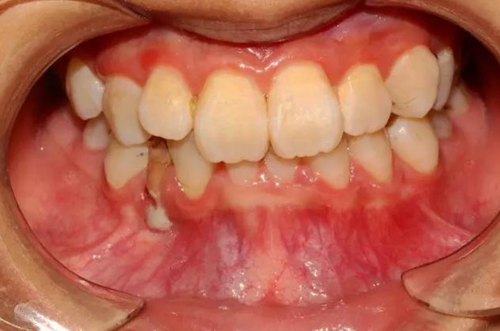

本案:患兒,女,14歲,因牙齒矯正來院,檢查見83滯留,43未見萌出,拍片發(fā)現(xiàn):43埋伏阻生于31、41、42根尖下方,按照正畸診療計(jì)劃,擬行43拔除術(shù)。

口腔牙列照片